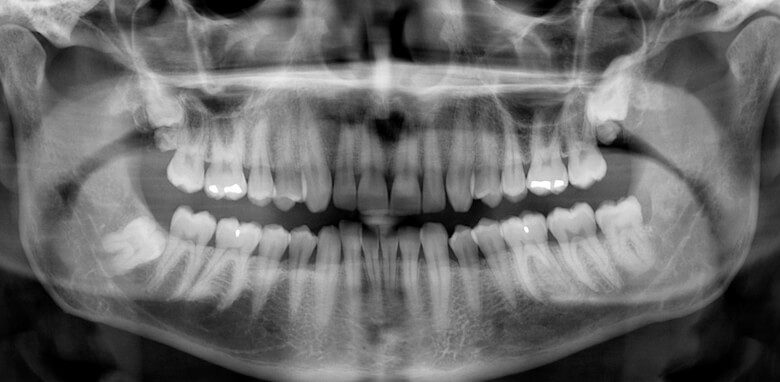

وی توضیح داد: میزان اشعه در رادیوگرافی‌های دندانی بسیار پایین است؛ برای مثال، میزان اشعه در یک رادیوگرافی داخل دهانی معمولی حدود ۰.۰۰۵ میلی‌سیورت و تصویر پانورامیک (OPG) حدود ۰.۰۲ میلی‌سیورت است که به ترتیب هزار و ۲۵۰ برابر کمتر از حد مجاز ۵ میلی‌سیورت در دوران بارداری است.

وی تصریح کرد: در تصویربرداری پانورامیک دندان (OPG)، استفاده از محافظ تیروئید توصیه نمی‌شود.

وی توضیح داد که تابش پرتو از پشت سر بیمار انجام می‌شود و قرار دادن محافظ می‌تواند سایه در نواحی چانه، ریشه دندان‌های قدامی یا فک پایین ایجاد کند؛ این موضوع کیفیت تصویر را کاهش داده و احتمال نیاز به تکرار عکس را افزایش می‌دهد که در نهایت میزان تابش اشعه را بالا می‌برد.